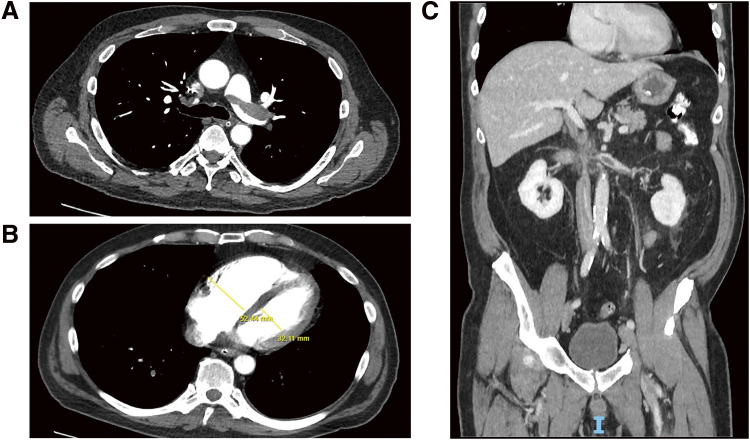

弥散性静脉血栓栓塞(VTE)常见于癌症患者,这些患者往往有全身溶栓的禁忌症,需要进行癌症手术。这样的临床情况往往是具有挑战性的管理。在本病例报告中,我们展示了一种创新的、单一的手术方法,用于切除广泛的静脉血栓栓塞,改善症状,预防血流动力学失代偿,并允许最低水平的抗凝治疗,以便必要的癌症手术可以安全地进行。

Disseminated venous thromboembolism (VTE) occurs commonly in cancer patients, who tend to have contraindications to systemic thrombolysis and require cancer surgery. Such clinical scenarios are often challenging to manage. In this case report, we illustrate an innovative, single procedural approach in such a patient to remove extensive VTE, improve symptoms, prevent hemodynamic decompensation, and allow for a minimal level of anticoagulation such that necessary cancer surgery can proceed safely.